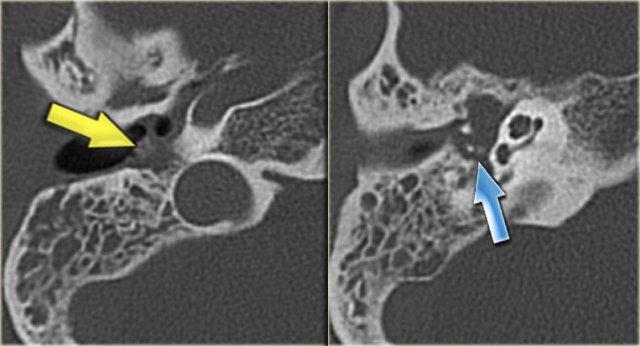

Gãy dọc (mũi tên vàng) đi qua xương chũm về phía vùng hạch gối. Trật xương đe với trật khớp búa-đe và khớp đe-bàn đạp (mũi tên xanh).

Hình ảnh bên trái của một nam bệnh nhân bị chấn thương đầu hai tháng trước.

Bệnh nhân than phiền về ù tai từng cơn.

Có đường gãy dọc (mũi tên vàng) đi qua xương chũm về phía vùng hạch gối.

Có trật xương đe với trật khớp búa-đe và khớp đe-bàn đạp (mũi tên xanh).

Không có tổn thương tai trong.

Tai trái để so sánh.

Hình ảnh bên trái của một nam bệnh nhân 54 tuổi, nhiều năm sau chấn thương đầu, kèm theo mất thính lực bên trái.

Có đường gãy ngang qua tiền đình và ống thần kinh mặt (mũi tên).

Ống bán khuyên ngoài bị lấp đầy một phần bởi chất đặc, phù hợp với viêm mê đạo cốt hóa.